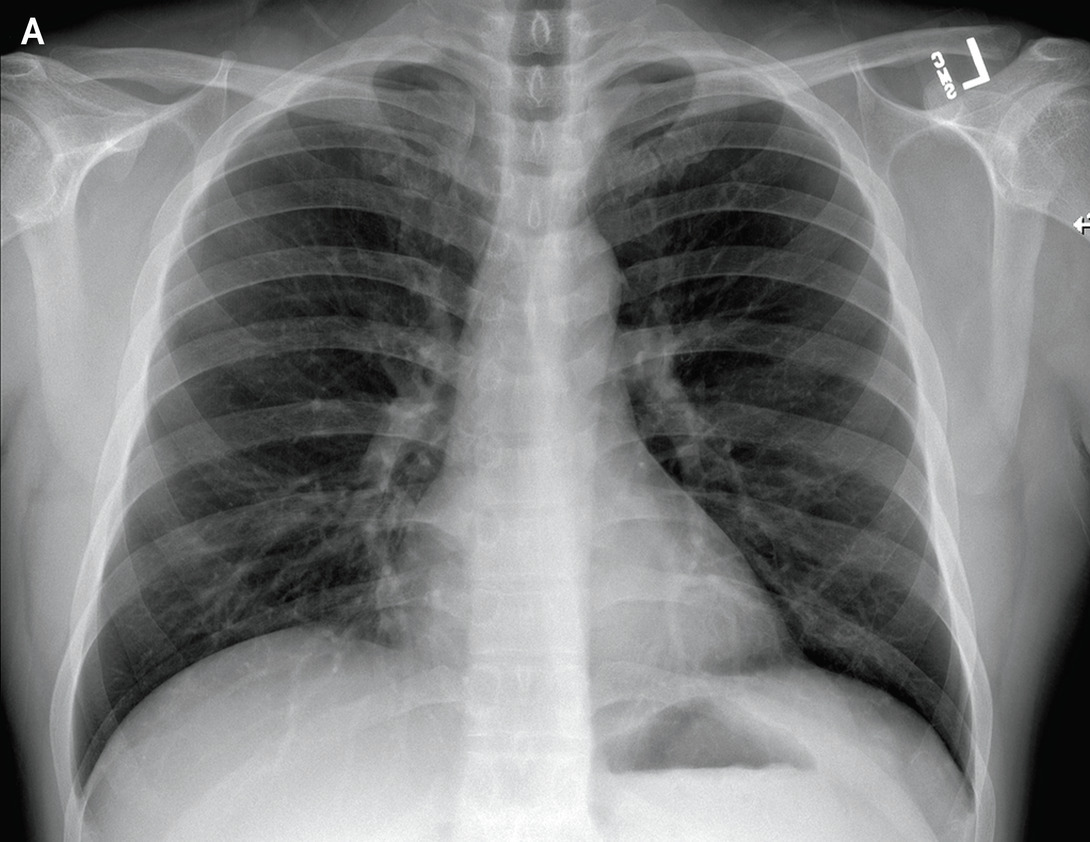

We employ a large-scale of chest X-ray dataset COVIDx [20] to validate the proposed model. It is comprised of 18,543 chest radiography images across 13,725 cases. Example chest X-ray images belonging to normal, pneumonia, and COVID-19 classes from COVIDx dataset are shown in Figure 2. When we examine these examples, we can differentiate these images in terms of features shown within areas marked by the blue circle since we can observe some lighter areas indicating COVID-19 infected regions in the blue circle.